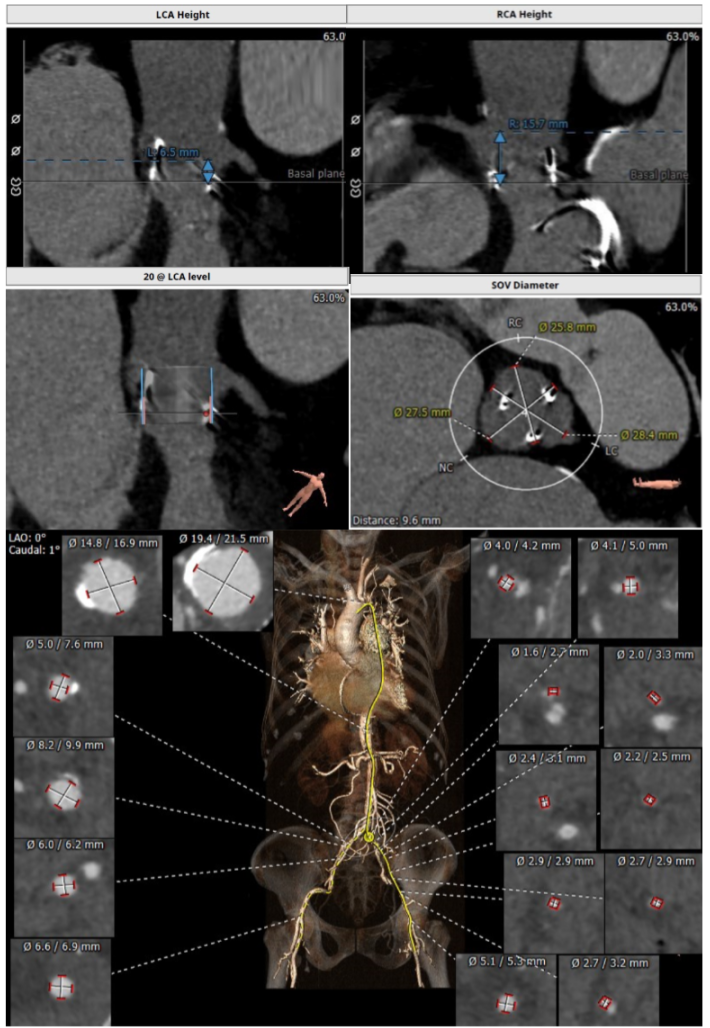

主瓣瓣中瓣CT评估

经过充分的术前食道超声及心脏CTA的评估,团队一致选择目前国际上瓣中瓣(Valve in Valve)技术使用最多最成熟的器械——Edwards SAPIEN3瓣膜。与林阿姨及其家属充分沟通后,在经验丰富的王焱院长的指导下,珠海市人民医院结构性心脏病团队决定为林阿姨同期进行主动脉瓣及二尖瓣的双瓣膜置换,采用的方案是先经股动脉途径为其行主动脉瓣的瓣中瓣植入(VinV TAVR),然后经股静脉途径,穿刺房间隔后,行二尖瓣的瓣中瓣植入(VinV TMVR),视情况对房间隔穿刺后的缺损进行封堵。